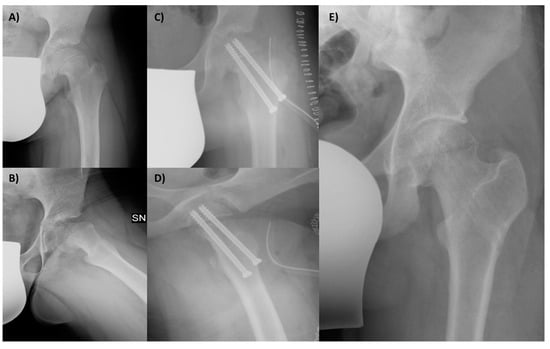

To evaluate the hip function, we used the Harris Hip Score (HHS) and hip joint articulation in the pre-operative period and at 3 and 6 months and 1 and 8 years follow-up. Anteroposterior and frog-leg lateral X-ray views were taken preoperatively and then at 4 weeks, 6 months, and yearly after. The level of slippage [] was recorded in the pre-operative period and at last follow-up (Figure 3). The lateral α angle [] and the epiphyseal–metaphyseal offset [] were also evaluated preoperatively and at the latest follow-up.

Figure 3.

A 12-year-old male patient affected by SCFE, with great deformity of the proximal femur, with a varus (A) and retroverted (B) neck. The femur after the surgery, with the correction in the coronal (C) and sagittal planes (D); the screws in both views are in the bone and not protrude into the joint. The final X-ray follow-up at 8 years shows the outcome of removing screws and the radiological good hip joint status (E).